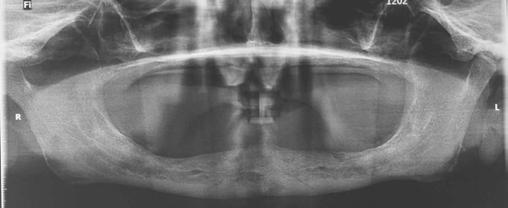

A 59-year-old male reported to the dental office with missing maxillary teeth due to poor oral hygiene. Treatment planning was done for all on four implant placements followed by prosthesis. A complete medical history was obtained and was negative for any significant medical problems. The patient denied being allergic to any medication as well. The patient agreed to the implant placement and was advised to have an orthopantomogram (Figure 1).

on the crest of the ridge in the region of teeth Nos. 15-25. While creating the incision, bleeding was noticed in the region of tooth No. 15 which intensified during the flap reflection (Figure 2). Bleeding was pulsatile, indicating an arterial bleed. Initially attempts to control bleeding included a pressure pack and ice pack, and the bleeder was isolated, and the vessel ligated (Figure 3). The bleeding could be controlled, and the procedure was completed by placing four Bioner implants (Bioner, Spain), size 4/10 mm. Sutures were placed, and patient was kept on basic medication for pain and infection control. Immediately after the surgery, the patient was advised to get a CBCT. As shown in Figure 4, a coronal view and Figure 4B (yellow arrows), the position of the artery can be seen.

Figure 1: Pre-op panoramic radiograph Figure 2 (left): Alveolar antral artery (AAA). Figure 3 (center): The artery has been ligated with suture. Figures 4A and 4B (right): CBCT post-implant placement and position of the artery coronally (top). 4B. Showing the position of alveolar antral artery (AAA) in relation to implant placement as indicated by the yellow arrows (bottom)

Figure 5: Panoramic radiograph following implant placement